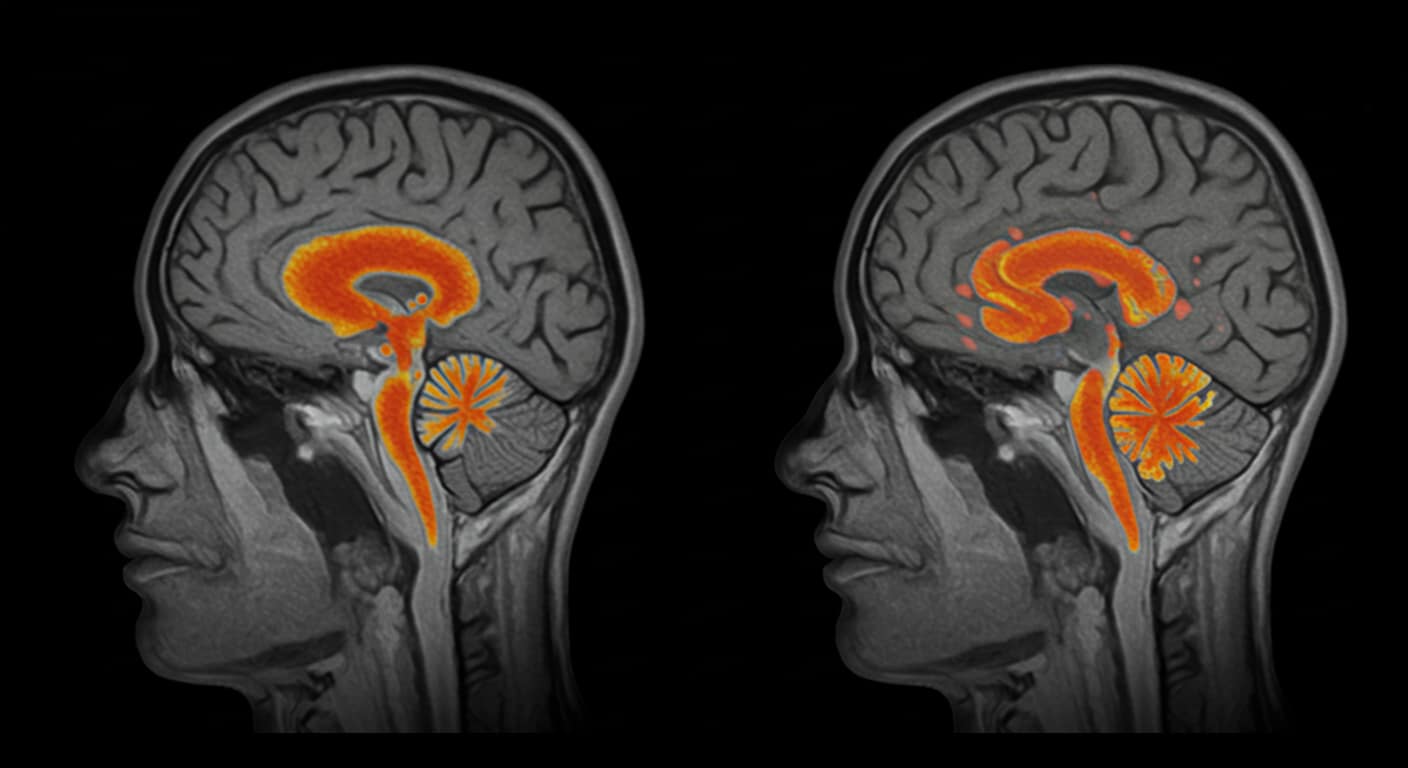

The Science: Sleep and Teen Brain Health

A study from Mount Sinai revealed that missing sleep for several consecutive days affects emotional regulation and can lead to long-term health issues. Teenagers who aren’t getting enough sleep feel overwhelmed and may struggle to perform even basic tasks. Sleep deprivation not only signals mental health struggles—it can also activate genes that cause inflammation in the body. This inflammation releases even more cortisol, creating a harmful cycle that worsens over time. Chronic sleep loss doesn’t just make a teen feel tired; it may contribute to clinical depression if left unaddressed.